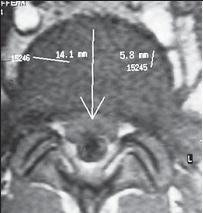

МРТ № 11

МРТ № 12

На МРТ № 11 наблюдается парамедианная грыжа межпозвонкового диска, которая как бы обхватывает с двух сторон спинной мозг

На МРТ № 12 наблюдается медианная (срединная) грыжа межпозвонкового диска, которая часто протекает безсимптомно и может достигать больших размеров